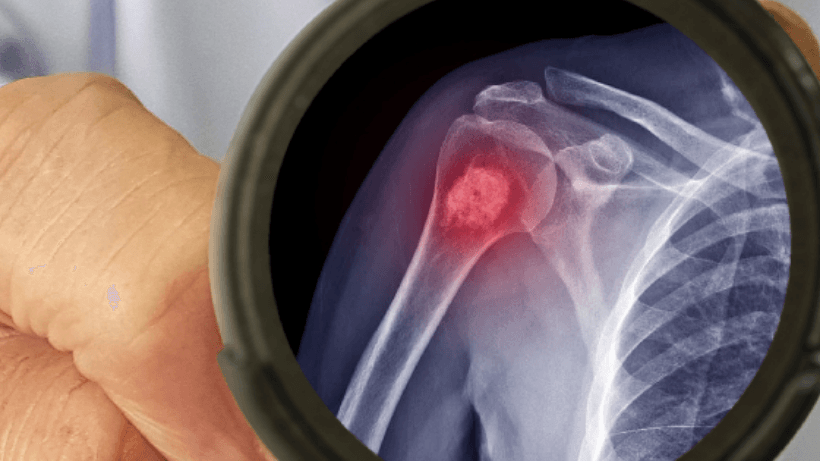

Sarcoma adalah sejenis kanser yang berkembang dalam tisu penghubung badan, termasuk otot, tulang, tendon, dan tulang rawan.. Tidak seperti kanser yang lebih biasa, sarkoma agak jarang berlaku. Walaupun sarkoma hanya menyumbang hanya peratusan kecil semua diagnosis kanser, mereka boleh berlaku di kedua -dua kanak -kanak dan orang dewasa. Jarang sekali mereka kadang -kadang boleh membuat diagnosis dan rawatan lebih mencabar.

b. Sarcomas Tulang:

- Osteosarcoma: Timbul dari sel tulang dan sering berlaku pada kanak -kanak dan orang dewasa muda, biasanya di lengan atau kaki.

- Chondrosarcoma: Membangun dalam sel rawan, biasanya pada orang dewasa yang lebih tua, dan boleh berlaku dalam tulang atau tisu lembut.

- Sarcomas Tulang: Sakit tulang, sering semakin teruk pada waktu malam atau dengan aktiviti. Bengkak atau kelembutan di tapak.

1. Ujian pengimejan (MRI, imbasan CT)

- Ia membantu menggambarkan tulang dan mengesan kelainan pada tisu lembut.